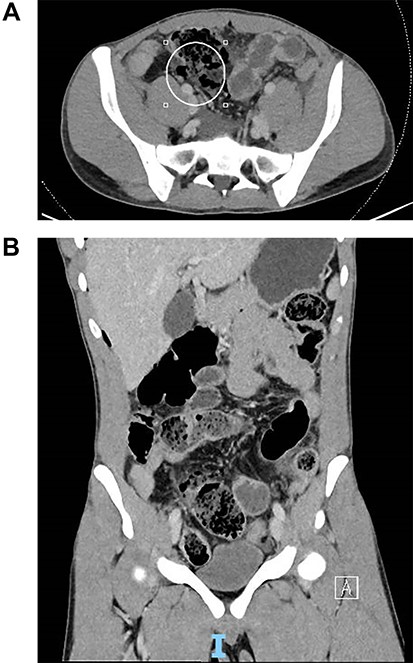

A chest x-ray noted a small amount of subdiaphragmatic air. A computed tomography showed small bowel perforation at the distal ileum with scattered segmental wall thickening and mild surrounding fat stranding involving the transverse colon, terminal ileum and distal ileum as shown in Fig. 1a and b.

(A) Coronal slice of computed tomography (CT) image of small bowel perforation at distal ileum. (B) Sagittal slice of CT image of small bowel perforation at distal ileum.